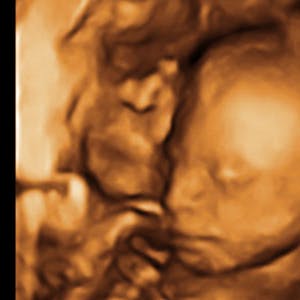

Gravid

Vi gør en dyd ud af at klæde dig godt på både før, under og efter din graviditet. Vi ved, at der kan komme mange spørgsmål til din graviditet, fødsel, amning, din babys udvikling og mange flere emner, derfor har vi samlet guides, tips & tricks samt læsernes egne fortællinger i dette gravid univers.